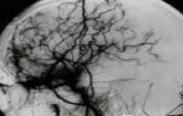

小儿脑血管畸形

628健康网为您分享有关小儿脑血管畸形的症状,小儿脑血管畸形的治疗方法,小儿脑血管畸形的预防知识,小儿脑血管畸形的症状...

小儿烟雾病

628健康网为您分享有关小儿烟雾病的症状,小儿烟雾病的治疗方法,小儿烟雾病的预防知识,小儿烟雾病的症状图片,小儿烟雾病...

脑动静脉畸形

628健康网为您分享有关脑动静脉畸形的症状,脑动静脉畸形的治疗方法,脑动静脉畸形的预防知识,脑动静脉畸形的症状图片,脑...